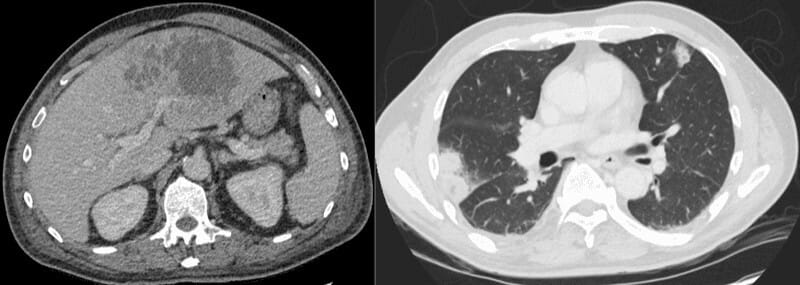

This is a CT scan showing a liver abscess within the liver parenchyma (left image) and multiple septic emboli (lung abscesses/nodules) scattered throughout both lungs (right image), consistent with disseminated infection.

- CT: Liver abscess shows a centrally hypodense lesion with peripheral ring (rim) enhancement (“double-target sign”); may contain gas; segmental perfusion abnormalities adjacent; multiple bilateral peripheral lung nodules or cavitary lesions representing septic emboli

- Signs: Double-target sign (central hypodense cavity, inner enhancing rim, outer hypodense edema) in liver abscess on contrast CT; Cluster sign (aggregation of multiple small abscesses coalescing) in liver; pulmonary septic emboli appear as multiple cavitary nodules